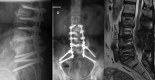

Spondylodiscitis is an uncommon but serious complication after spine surgeries, and its main etiologic agent is Staphylococcus aureus . Fungal infections are rare and mostly caused by Candida albicans . We report the clinical case of a 69-year-old male patient who underwent a L2-S1 arthrodesis for degenerative scoliosis correction. He presented an infection 2.5 months after the procedure, a spondylodiscitis at L5-S1 levels, caused by Candida parapsilosis . The treatment consisted of surgical material removal, tricortical iliac graft placement in an anterior approach (L5-S1), lumbopelvic fixation (from T10 to the pelvis) in a posterior approach, and drug treatment with anidulafungin and fluconazole. This last medication was administered for 12 months, with good clinical outcomes.